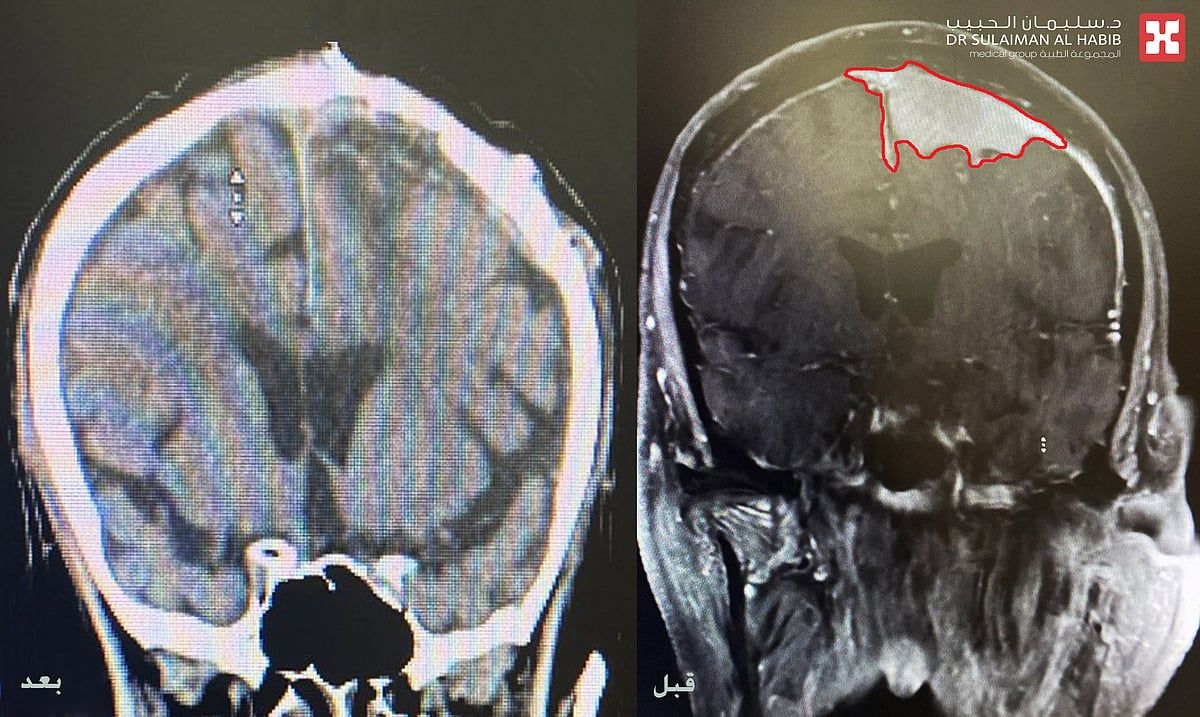

موضحاً أن الفريق الطبي أخضعه لحزمة من الفحوصات الطبية الدقيقة والتي شملت، الرنين المغناطيسي (M.R.I) والتصوير الطبقي لشرايين الدماغ (CT angiography)، وقد كشفت النتائج عن وجود ورم كبير بحجم (6×5×6) سم متمركز في منتصف الدماغ بالقرب من مراكز منطقة الحركة للأطراف العلوية والسفلية ومتداخل مع الشريان الأعظم، كما نتج عن هذا الورم حدوث إزاحة وضغط شديد على الدماغ ووجود انسداد في عدد من الشرايين المحيطة به.

وقال الدكتور هاني عبد العزيز في اليوم الثالث تحسنت حالة المراجع ،حيث تم نقله لجناح التنويم، مع إخضاعه لفحوصات بالتصوير المقطعي، والتي أثبتت استئصال الورم بشكل كامل ونجاح العملية وانتهاء نوبات التشنج والحركات اللارادية، وخرج من المستشفى في اليوم الرابع وهو بصحة جيدة.